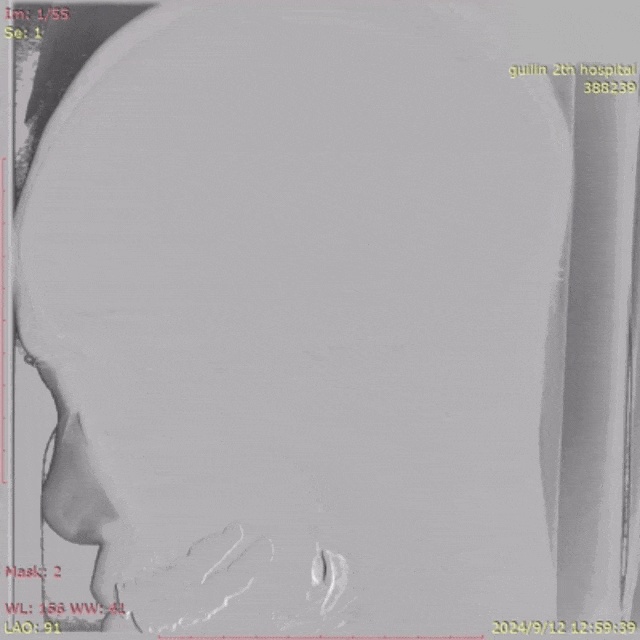

术前术后DSA侧位即刻对比

脑血管造影提示患者患有左侧颈内动脉-后交通动脉瘤(瘤颈累及脉络膜前动脉),瘤体大小约12mm*7.8mm,宽径,合并子瘤,双侧胚胎型大脑后动脉(PHASES=11分);术前高分辨MR血管分析提示:管壁动脉粥样硬化,动脉瘤子瘤瘤壁强化

术后,患者动脉瘤达到Raymond II级,颈内动脉-后交通动脉-脉络膜前动脉血运正常。手术用时约两小时,蒋女士术后第二天即可下床活动。